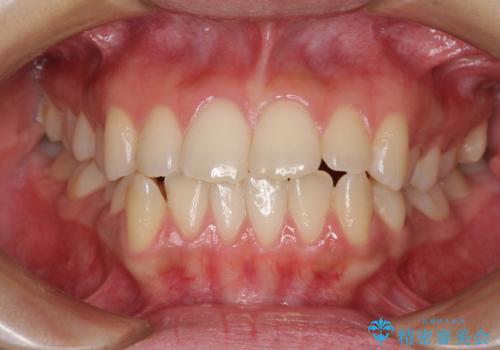

[インビザライン] 前歯のガタつき・すれ違い マウスピース矯正治療